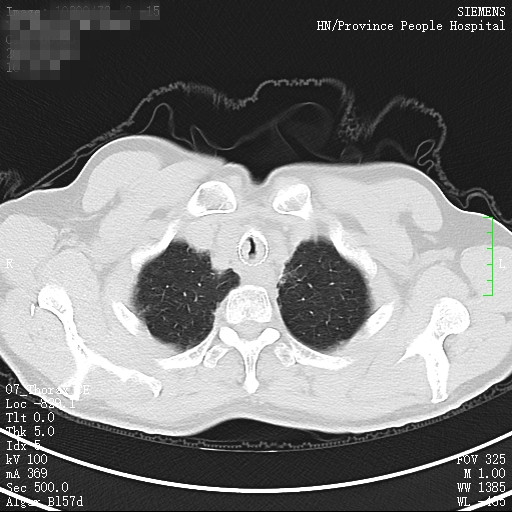

59岁的黄先生是一名气管鳞癌患者,3年前曾在捷克论坛 呼吸二病区接受了紧急支气管镜手术,做了气管内肿瘤切除并置入金属支架,此次黄先生再次出现呼吸窘迫症状,当地医院立即联系将其转入呼吸二病区准备再次介入治疗。

完善术前检查后即将安排手术时,黄先生的健康码突然变为黄码,但其气管最窄段不足5mm,极度呼吸窘迫,手术不做,则生命危在旦夕,做,有暴露于病毒的可能。为此,呼吸二病区张卫东主任立即组织专家讨论,疫情面前,医务人员必须站在第一线,生命至上,创造一切条件积极介入治疗,挽救患者的生命。

呼吸内科二病区立即启动红黄码管理预案流程,将患者转入应急隔离病房,同时向医务部、感控办报备,组织最精干力量按照三级预防措施于应急隔离病房行床旁介入手术。介入学组刘志光主任医师,邓红英副主任护师及谭建龙副主任医师严格按照三级防护措施,于床旁为患者行了支气管镜下气道肿瘤切除。术后在院感部门指导下对该应急隔离病房及操作器械进行了终末消毒。黄先生在术后呼吸困难症状迅速缓解,生活可以自理。术后第三天健康码转为“绿码”,安全出院。